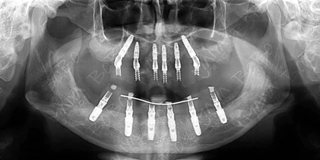

手术CT片